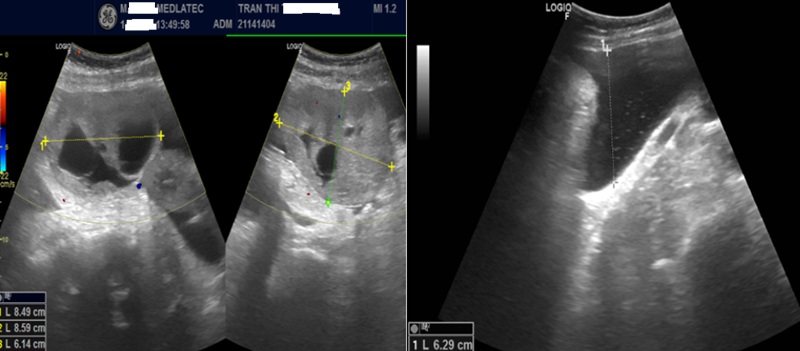

Kết quả, xét nghiệm dấu ấn ung thư thấy nồng độ CA 125 tăng cao ở mức 399 U/mL (giá trị bình thường 0–35) và HE4 là 469 pmol/L (bình thường <60,5). Siêu âm ghi nhận, hình ảnh khối hỗn hợp âm vùng tiểu khung, theo dõi u buồng trứng trái kèm dịch tự do ổ bụng.

Hình ảnh siêu âm ổ bụng của bệnh nhân

Trên phim chụp cộng hưởng từ (MRI), phát hiện khối cạnh trái tử cung, nhiều dịch tự do ổ bụng, được phân loại O-RADS 5 – nhóm nguy cơ ác tính cao, đồng thời ghi nhận thêm khối vùng cổ tử cung.